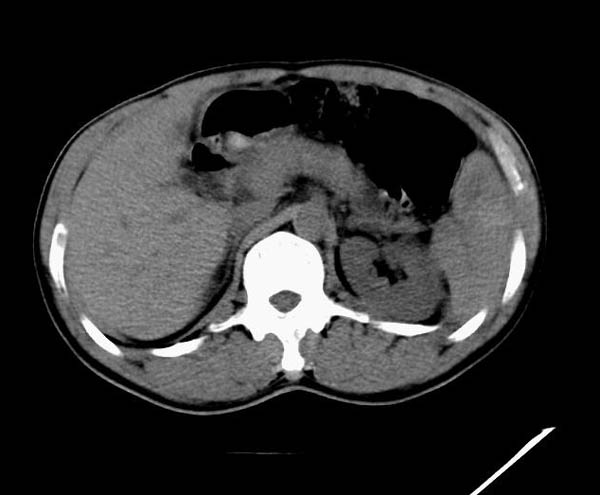

m50y以腹疼、腹胀2小时就诊。腹透肠胀气较明显,余无明显异常。做ct时腹疼已明显缓解;病人否认外伤史,否认血液病变、否认肝炎史。建议第二天做ct增强,病人第二天放弃了增强。脾脏区较高密度影ct值为60hu,正常脾脏ct值为45hu(窗宽:150,窗位:56)。

ct表现:脾脏内见较高密度影ct值为60hu,正常脾脏ct值为45hu(窗宽:150,窗位:56)。 边界清晰,周围见略低密度影

脾脏实质内高密度病变,ct值为60hu,边界清晰,无明显外伤病史,腹痛、腹胀2小时就诊,首先考虑脾脏血管瘤破裂出血。